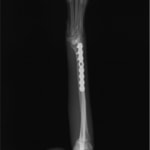

トイプードル 右遠位橈尺骨短斜骨折のALPSによる内固定

Locking Compression Plate

LCPは、スクリュー(ネジ)とプレート(金属の板)をロックする特殊な構造により骨折部位を固定する新しい世代のプレートシステムです。ひとつのホールでロッキングスクリューとスタンダードスクリューの使用を選択できるユニークな構造をしているため、骨折断端間の圧迫を目的とした従来型プレート固定法に加え、高い角度安定性を有するロッキングスクリューを用いた固定法の選択が可能です。従来のプレートシステムでは困難だった部分の骨折や癒合不全の症例に高い治療効果をもたらします。